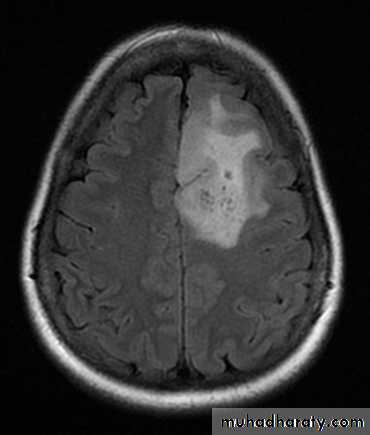

OLIGODENDROGLIOMA AXIAL MRI